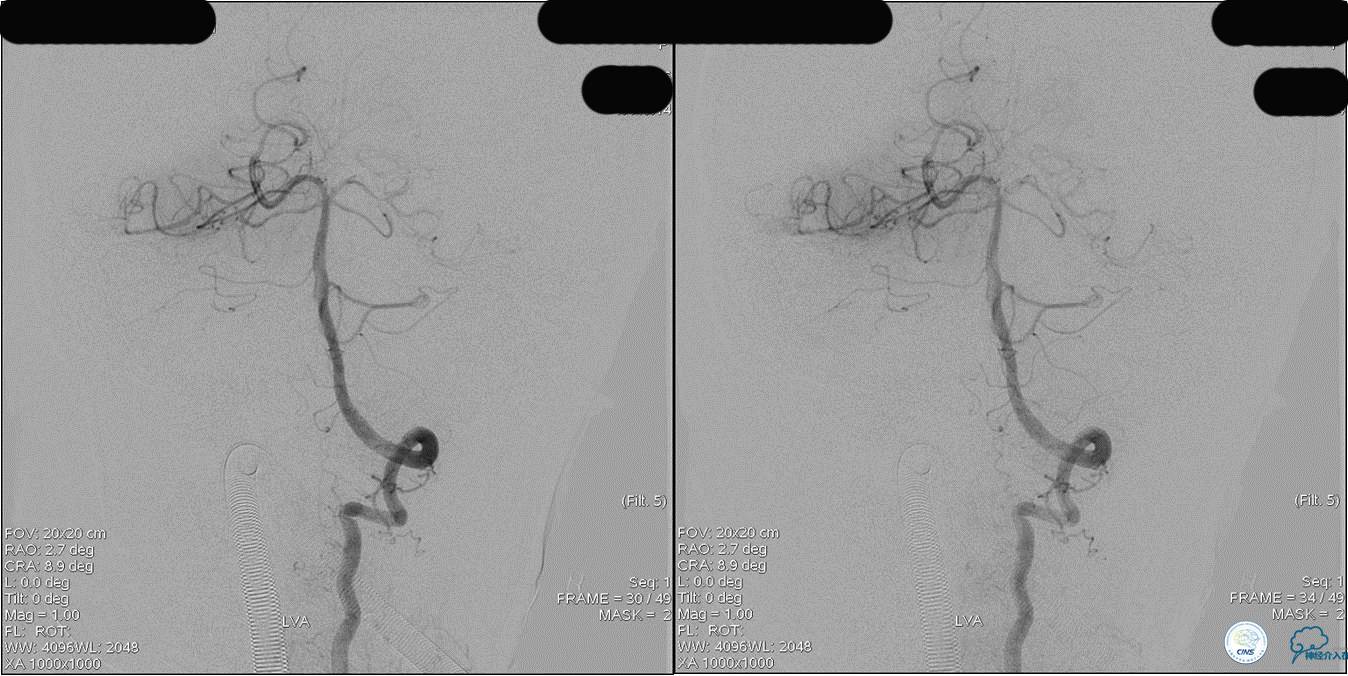

》DSA资料(左侧椎动脉)

》DSA资料(右侧椎动脉)